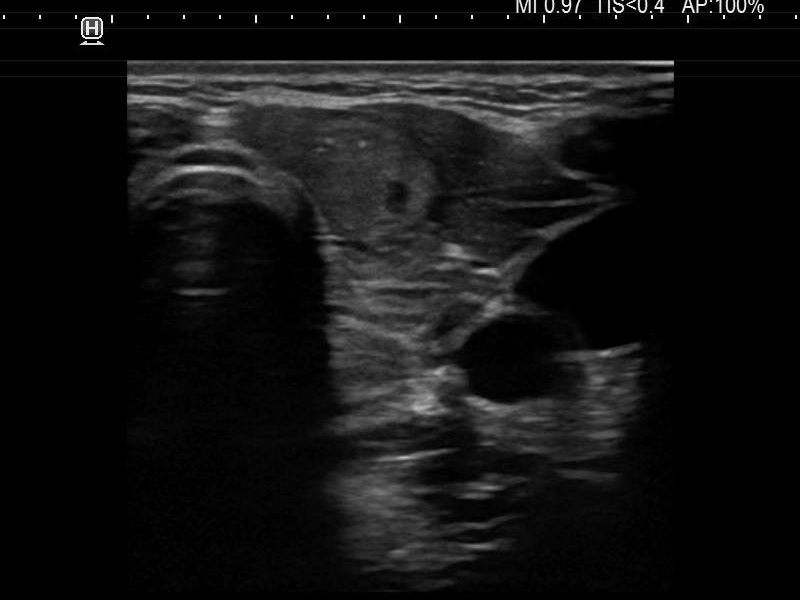

Ultrasonography. The thyroid was moderately hypoechoic and presented with numerous more and less hypoechoic discrete lesions. The largest of the latter was in the lower ventromedial part of the left lobe and had cystic areas and intranodular echogenic figures. The latter included typical comet tail artifacts, back wall cystic figures and some ambiguous small bright granules. The lesion showed both perinodular and intranodular vascularity. Compared with the former examination the nodule increased by 22% in volume. This difference is within the intraobserver variation.

Comment. Based on the presence of typical comet-tail artifacts, the questionable punctate echogenic granules are worth considering also colloid crystals.